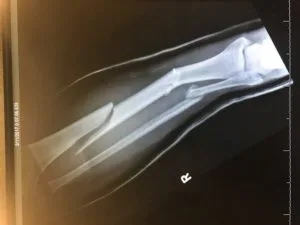

I didn’t need to know my lower right leg was bent at enough of a grotesque angle that my tibia and probably fibula were broken. I didn’t need to know my nose was bent over an inch to the left, that my eyes were becoming black. That I was lying in a pool of my own blood on the side of a mountain.

A few X-Rays later, it was clear that my pain was real, my situation dire and being in the ER was exactly what I needed. Jim sat in a chair, never leaving my side.